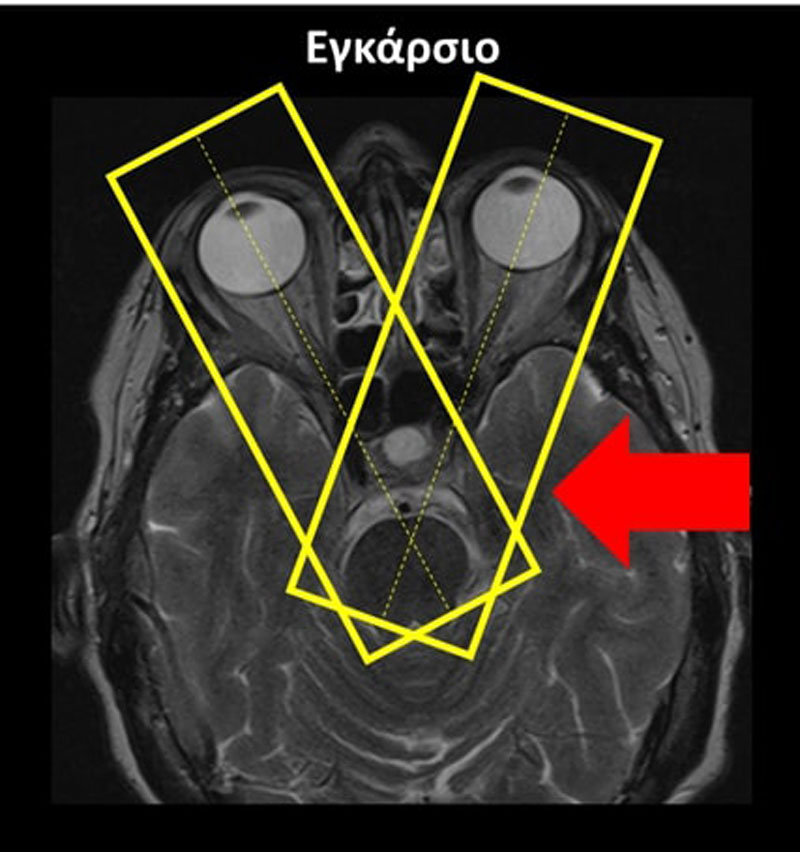

Εγκάρσιο (Axial/Transversal): οι εγκάρσιες τομές σχεδιάζονται παράλληλα με τη νοητή γραμμή που ενώνει τα δύο οπτικά νεύρα στο στεφανιαίο επίπεδο και παράλληλα με τα οπτικά νεύρα στο οβελιαίο επίπεδο. Κάποιες φορές το οπτικό νεύρο του δεξιού οφθαλμικού κόγχου έχει διαφορετική κλίση από το οπτικό νεύρο του αριστερού οφθαλμικού κόγχου στο οβελιαίο επίπεδο. Σε αυτή την περίπτωση, οι εγκάρσιες τομές σχεδιάζονται παράλληλα με το οπτικό νεύρο του οφθαλμικού κόγχου ενδιαφέροντος. Οι τομές πρέπει να περιλαμβάνουν ολόκληρη την περιοχή των οφθαλμικών κόγχων, από πάνω έως κάτω.